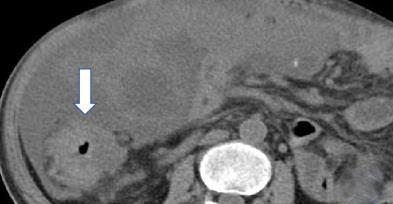

• 计算机体层摄影血管造影在腹腔镜结肠癌根治术前评估中的应用效果

2025, 31(6):24-31. DOI: 10.12235/E20240177

摘要 (181) HTML (147) PDF 4.65 M (171) 评论 (0) 收藏

摘要:目的 分析计算机体层摄影血管造影(CTA)在腹腔镜结肠癌根治术前评估中的应用效果。方法 回顾性分析2021年1月-2024年2月于该院接受腹腔镜结肠癌根治术的120例患者的临床资料。其中,60例行常规腹部CT和CTA,60例行磁共振成像(MRI)。以术后病理为金标准,判断CTA对临床T分期与术后病理的一致性,以及评估肿瘤是否侵犯肠系膜血管和周围组织的准确度。结果 术前CTA诊断T分期的准确率为95.00%(57/60),一致性好(Kappa = 0.925,P < 0.05);术前MRI诊断结肠癌T分期的准确率为98.33%(59/60),两者比较,差异无统计学意义(χ2 = 0.26,P > 0.05)。CTA预判肿瘤是否累及肠系膜上动脉、肠系膜上静脉、肠系膜下动脉、肠系膜下静脉、腹主动脉、肾动脉、肾静脉和脾动脉等血管,与术后病理的一致性好。特别是在预测肠系膜血管受累方面,CTA的敏感度为94.44%,特异度为95.83%,准确度高达95.00%。结论 对于行腹腔镜结肠癌根治术的患者,术前CTA不仅能清晰地显示结肠癌T分期,还能揭示肠系膜血管的走行和变异,以及肿瘤与周围组织的关系和侵犯程度,从而为手术规划提供强有力的支持,确保了腹腔镜手术的安全性,减少了不必要的手术风险。